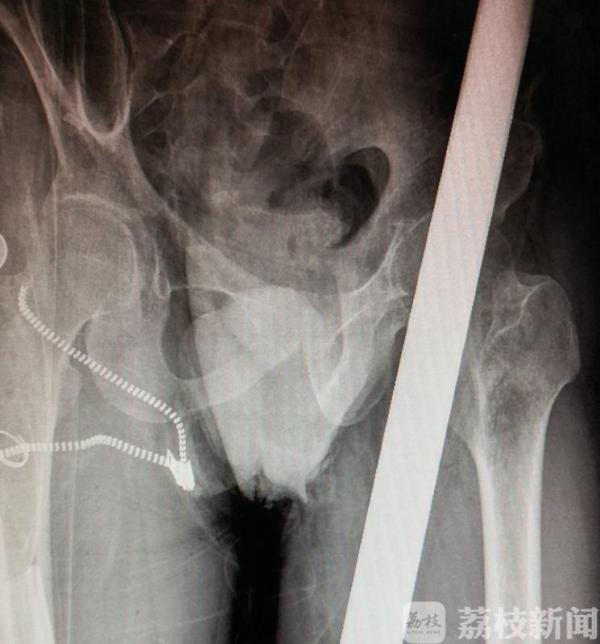

41岁的李先生(化名)是一名建筑工人,9月8日下午5点半,他在工地从8米高处坠落,一根直径10厘米,长一米多的钢管贯穿其左腿和臀部。幸运的是,钢管与坐骨神经和盆腔“擦肩而过”,经南京市第一医院骨科、麻醉科、重症医学科等多科医生奋力抢救,李先生在这罕见的人体贯穿伤里侥幸生还,手术10天后可以下地站立。目前李先生已经康复出院。

接诊的南京市第一医院骨科副主任医师杨蓊勃介绍:“当时遇到了一个非常棘手的问题,钢管露在上面是1/3,中间身体里是1/3,从臀部出来又是1/3,不管从哪一头拔都不好。钢管外面还套了塑料套,两头都很大,直接拔是没有办法拔出的。”

手术医生杨蓊勃决定,在保护重要脏器的情况下,用手从里往外推出钢管。这个动作必须要快,而且保持平稳,避免造成二次伤害。骨科副主任医师吴晓曙正好前一台手术刚结束,主动留下来参与手术。两位专家通过手工切开钢管侧面的肌肉,把肌肉拉开以后,把钢管用无菌敷料包好推出体外,整个过程不到半个小时。

杨蓊勃说,幸运的是,钢管基本没有伤及到重要器官,离坐骨神经就差一公分,只要再偏一点就能把盆腔击穿,坐骨神经如果打断,左腿也就面临截肢的危险。

钢管取出以后,专家立刻为其准备手术。取管后,被钢管压迫的血管得到释放,这让手术台上的医生捏了一把汗,为避免血管出血,医生快速将出血血管缝合。整个手术仅用了一个小时。